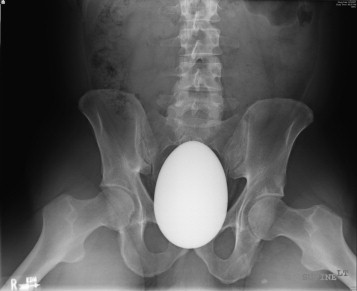

Pelvic X-ray of a 41-year-old male patient, previously fit and well. But what on EARTH is going on here?

Ah. That's what's wrong. An egg-shaped piece of marble is what's wrong. And the marijuana-based removal regime failed to work, you say?

This was, in all seriousness, a major surgical challenge. The object was too large and smooth to be removed from the rectum via the anus. It would not fit through the pelvic opening, and the surgeons felt it was also impossible to remove via the peritoneal cavity. What to do?

In desperation they consulted orthopaedics (!) and an ortho surgeon scrubbed in & divided the pubic symphysis, which was stretched open with a retractor to 4 cm. This gave enough space for the marble egg to be removed through the anus, using obstetric forceps. Phew!

Here is this extraordinary foreign body, measuring 12x8x8 cm. It was a long and complicated surgical procedure but the patient made a full recovery and left hospital 4 days later.